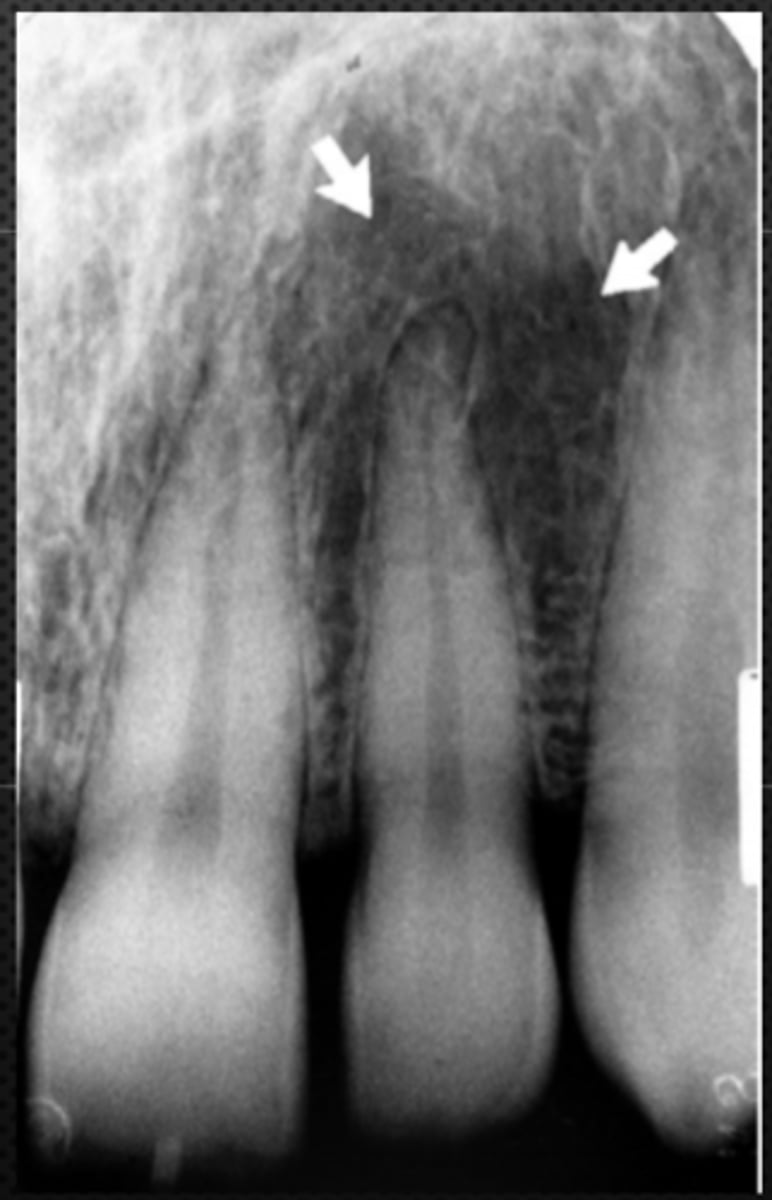

Black arrow - Nasal septum

White arrow- nasal conchae

Identify both structures

<p>Identify both structures</p>

Superior foramina of the Nasopalatine canal

Identify the structure

<p>Identify the structure</p>